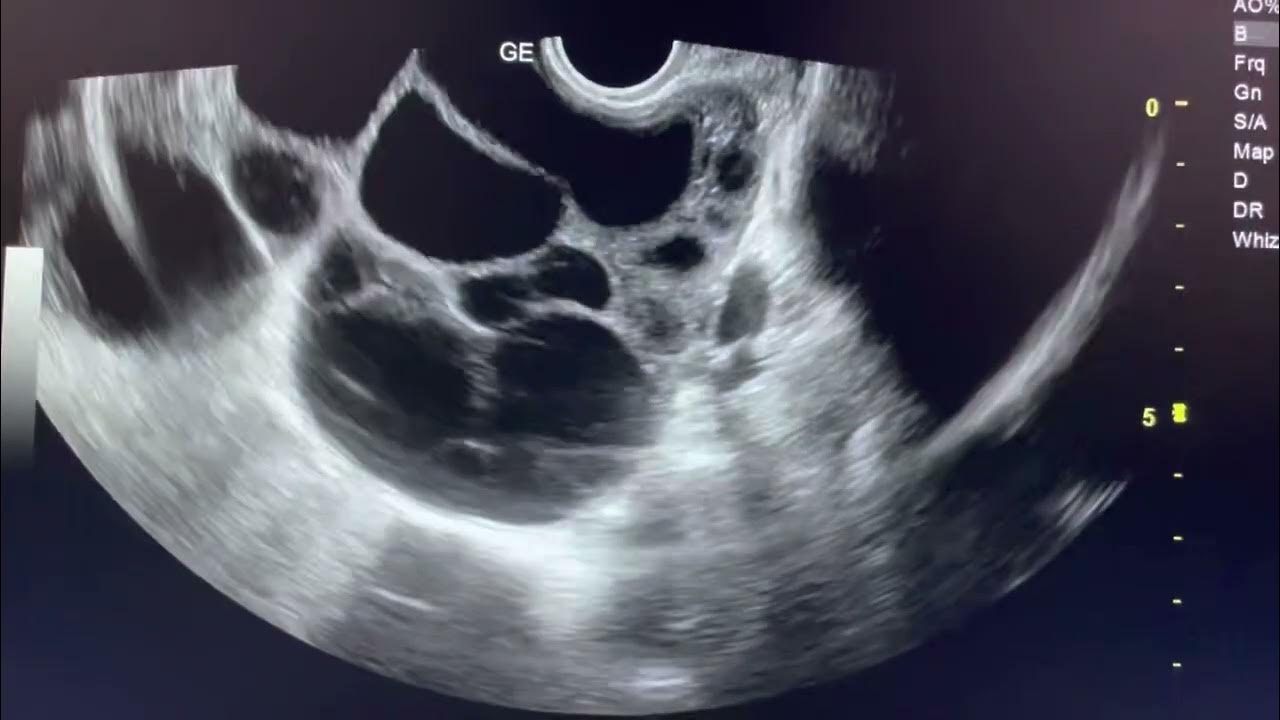

Ultrasound Case 213 Ruptured Ovarian Cyst YouTube

OVARIAN HYPERSTIMULATION SYNDROME Ultrasound ovariancyst sonography